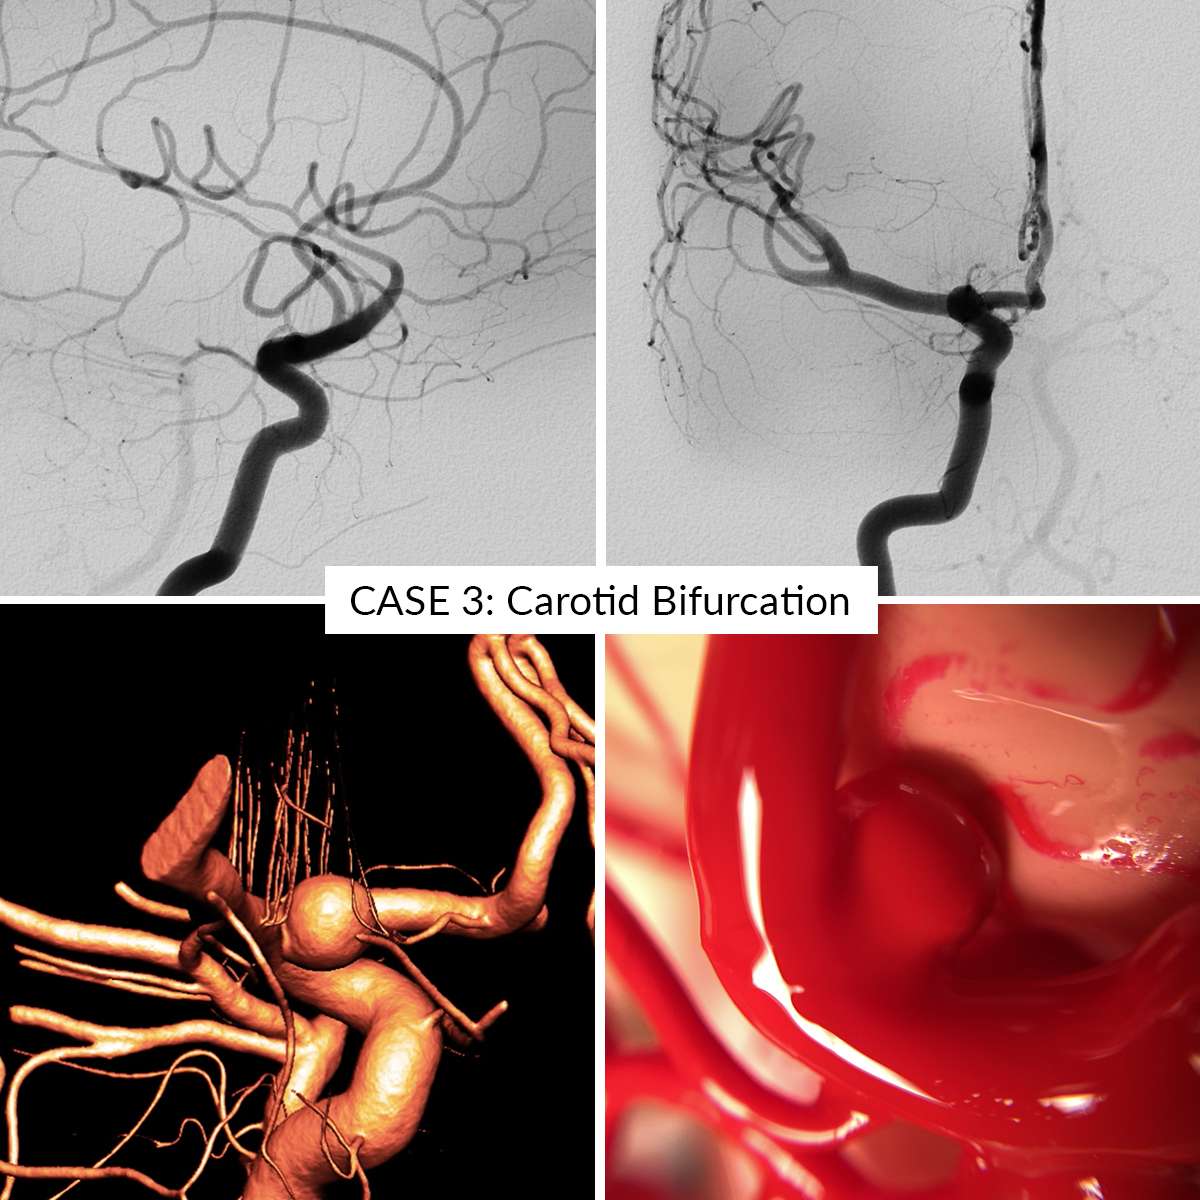

Case 3 : Carotid Bifurcation

- Case 3: Carotid Bifurcation